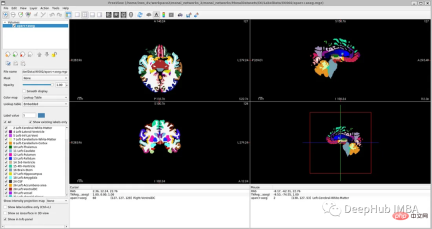

<code>image_filename = root_dir + '/Oasis_Data_Processed/OAS1_0001_MR1_mpr_n4_anon_111_t88_masked_gfc.nii' label_filename = root_dir + '/Oasis_Labels_Processed/OAS1_0001_MR1_mpr_n4_anon_111_t88_masked_gfc_fseg.nii' subject = torchio.Subject(image=torchio.ScalarImage(image_filename), label=torchio.LabelMap(label_filename)) subject.plot()</code>

因为OASIS-1数据集只有3个大脑结构标签,对于更详细的分割,理想的情况是像他们在研究论文中那样对28个皮质结构进行注释。在OASIS-1下载说明中,可以找到使用FreeSurfer获得的更多大脑结构的标签。

为了简化本教程,我们将使用以下标签,比OASIS-1但是要比FreeSurfer的少:

- Label 0: Background

- Label 1: LeftCerebralExterior

- Label 2: LeftWhiteMatter

- Label 3: LeftCerebralCortex